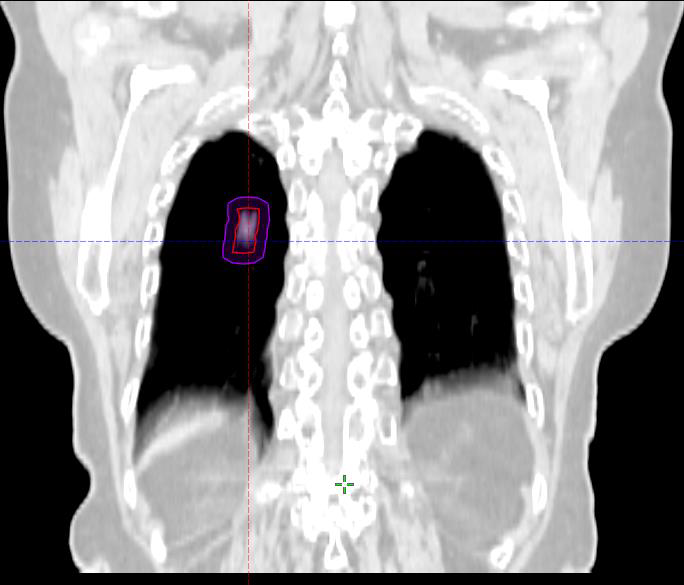

L’arrivée de la simulation virtuelle par scanner conjuguée aux techniques d’imagerie numériques que sont la TEP (Tomographie par émission de positons) ou l’IRM (Imagerie par résonance magnétique) a permis de franchir un pas très important dans la qualité de repérage des tumeurs et des organes à risques. L’imagerie TEP est une imagerie fonctionnelle. Elle montre dans le corps du patient l’image des cellules tumorales qui consomment et retiennent davantage un sucre radioactif à base de fluor 18 (18F-FDG Fluoro-DesoxyGlucose) que les cellules saines. Cette technique apporte une précision nouvelle parce qu’elle permet de visualiser la tumeur active, de vérifier l’envahissement ganglionnaire, et de détecter des métastases.

Fusion TEP/scanner pour la préparation d’un traitement de métastase pulmonaire